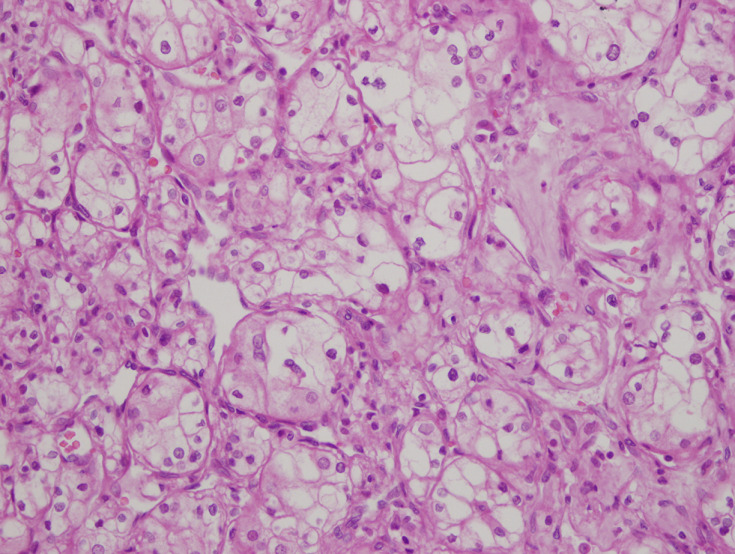

肾脏的功能受到其他器官疾病的影响。在这里,我们提出了一个肾功能正常的老年透析前患者,尽管有许多合并症,但肾脏学随访10年。患者男性,75岁,高血压病史15年,吸烟60包年,诊断为肌肉浸润性膀胱癌(MIBC)和左肾同步中央定位透明细胞肾细胞癌(ccRCC)。入院时患者估计肾小球滤过率(Glomerular Filtration Rate, eGFR) (CKD-EPI-cre)为54mL/min/1.73m2,左肾切除术后患者的eGFR降至35ml /min/1.73m2。经过10年的随访,患者的右肾功能正常,eGFR为24 mL/min/1.73m2,尽管进行了根治性膀胱切除术并尿路转移、根治性肾切除术、重度吸烟、心肾综合征、慢性阻塞性肺疾病和高血压。众所周知,高血压、吸烟、癌症、感染、肺病和心脏病等合并症会造成不可逆的肾脏损害,并会导致肾功能下降。这些合并症的适当和早期诊断和治疗可以使肾脏健康老化,而不需要透析。

Kidneys are functionally affected by the diseases of other organs. Here, we present an elderly predialysis patient with a functioning kidney for 10 years of nephrological follow-up despite many comorbidities. A 75-year-old male patient with a medical history of hypertension for 15 years and 60 pack years of cigarette smoking, was diagnosed as muscle invasive bladder cancer (MIBC) and synchronous centrally located clear cell renal cell carcinoma (ccRCC) in the left kidney. At admission, the patient had an Estimated Glomerular Filtration Rate (eGFR) (CKD-EPI-cre) of 54mL/min/1.73m2, after left nephrectomy eGFR of the patient decreased to 35 mL/min/1.73m2. After ten years of follow-up, the patient's right kidney had been functional with a eGFR of 24 mL/min/1.73m2 despite radical cystectomy with urinary diversion, radical nephrectomy, heavy smoking, [cardiorenal syndrome, chronic obstructive pulmonary disease, and hypertension. It is well known that comorbidities such as hypertension, smoking, cancers, infections, pulmonary and heart diseases contribute to irreversible kidney damage and are additive to decreasing kidney function. Appropriate and early diagnosis and treatment of these comorbidities permit healthy aging of the kidneys without the need for dialysis.